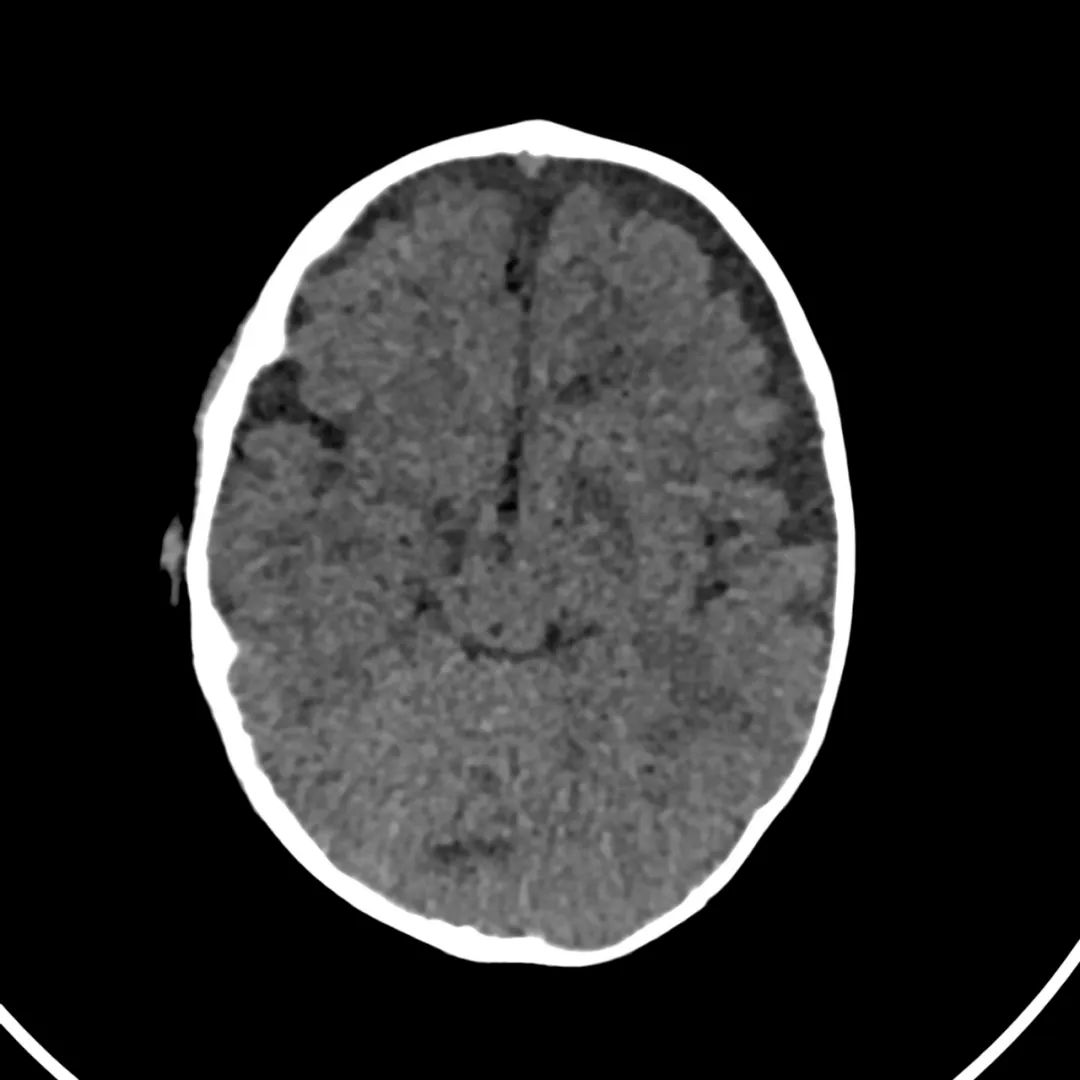

脑部CT检查显示扁豆状核内有略对称的低密度区。

印象:通过将这些成像模式与临床和实验室检查结果相结合,就有可能得出低血糖性脑病。

影像影响内囊后肢、大脑皮层(特别是枕叶和岛叶)、海马和基底节区,常是双边对称性的。